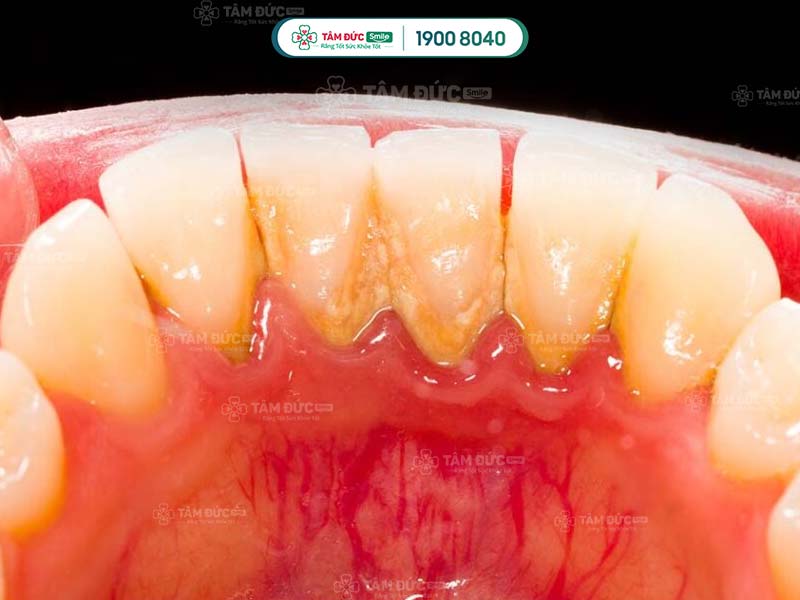

- Phát hiện có nhiều cao răng và mảng bám ở thân răng hoặc dưới nướu.

Cao răng không phải là nguyên nhân trực tiếp gây ra các bệnh lý về răng miệng, nhưng lại là nơi trú ngụ của nhiều loại hại khuẩn. Vì vậy, cao răng tạo điều kiện để vi khuẩn gây bệnh.

Cao răng tích tụ lâu ngày sẽ gây ra các bệnh lý như: Sâu răng, viêm nướu, tụt nướu, mòn men răng, viêm nha chu,... Do đó, cạo cao răng thường xuyên giúp Quý khách ngăn chặn vi khuẩn phát triển, giảm nguy cơ mắc phải các bệnh lý răng miệng.